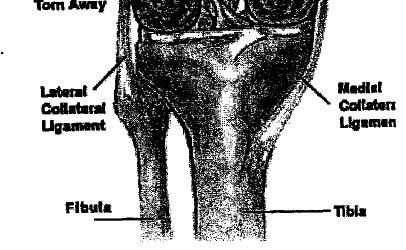

Osteoarthritis is a common problem for many people. Osteoarthritis is sometimes referred to as "degenerative joint disease", or wear-and-tear arthritis. The main problem in osteoarthritis is degeneration of the articular cartilage that covers the joint. This results in areas of the joint where bone rubs against bone. Bone spurs may form around the joint as the body's response. Osteoarthritis may result from an injury to the knee earlier in life. Fractures involving the joint surfaces, instability from ligament tears, and meniscal injuries can all cause abnormal wear and tear of the knee joint.

The diagnosis of osteoarthritis can usually be made on the basis of the initial history and examination. X-Rays are very helpful in the diagnosis and may be the only special test required in the majority of cases. In some cases of early osteoarthritis, the X-rays may not show changes typical of osteoarthritis. It is not always clear where the pain is coming from. Knee pain from

osteoarthritis may be confused with other common causes of knee pain such as a torn meniscus or kneecap problems. Sometimes, a MRI scan may be ordered to look at the knee more closely. A MRI scan is a special radiological test where magnetic waves are used to create pictures that look like slices of the knee. The MRI scan shows more than the bones of the knee. It can show the ligaments, articular cartilage, and menisci as well. The MRI scan is painless, and requires no needles or dye to be injected.